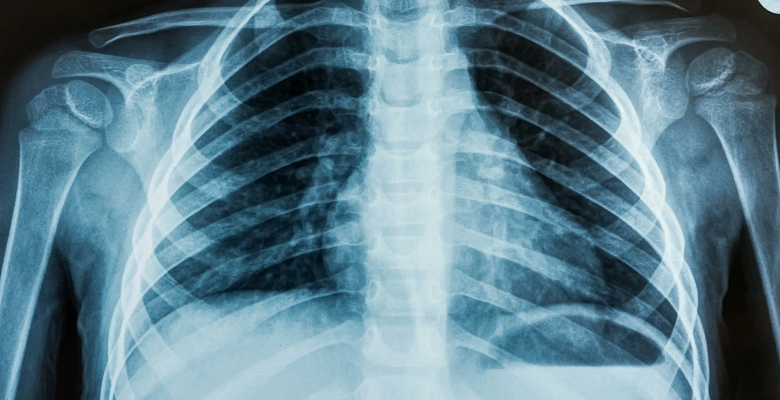

Рентен органов грудной клетки

Рентгенография грудной клетки — это неинвазивное исследование, при котором с помощью рентгеновского излучения получают изображения внутренних органов. Этот метод широко используется для диагностики заболеваний дыхательной системы, сердца и крупных сосудов, а также для оценки состояния рёбер и позвоночника.